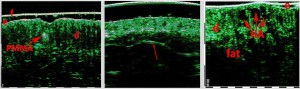

-Έγχυση Πληρωτικών Υλικών (Fillers)

-Lifting με νήματα

-Μέθοδοι θεραπείας υψηλής ενέργειας

(λέιζερ, RF-Ραδιοσυχνότητα, HIFU-Υψηλής Έντασης Εστιασμένος Υπέρηχος, κ.λπ.)